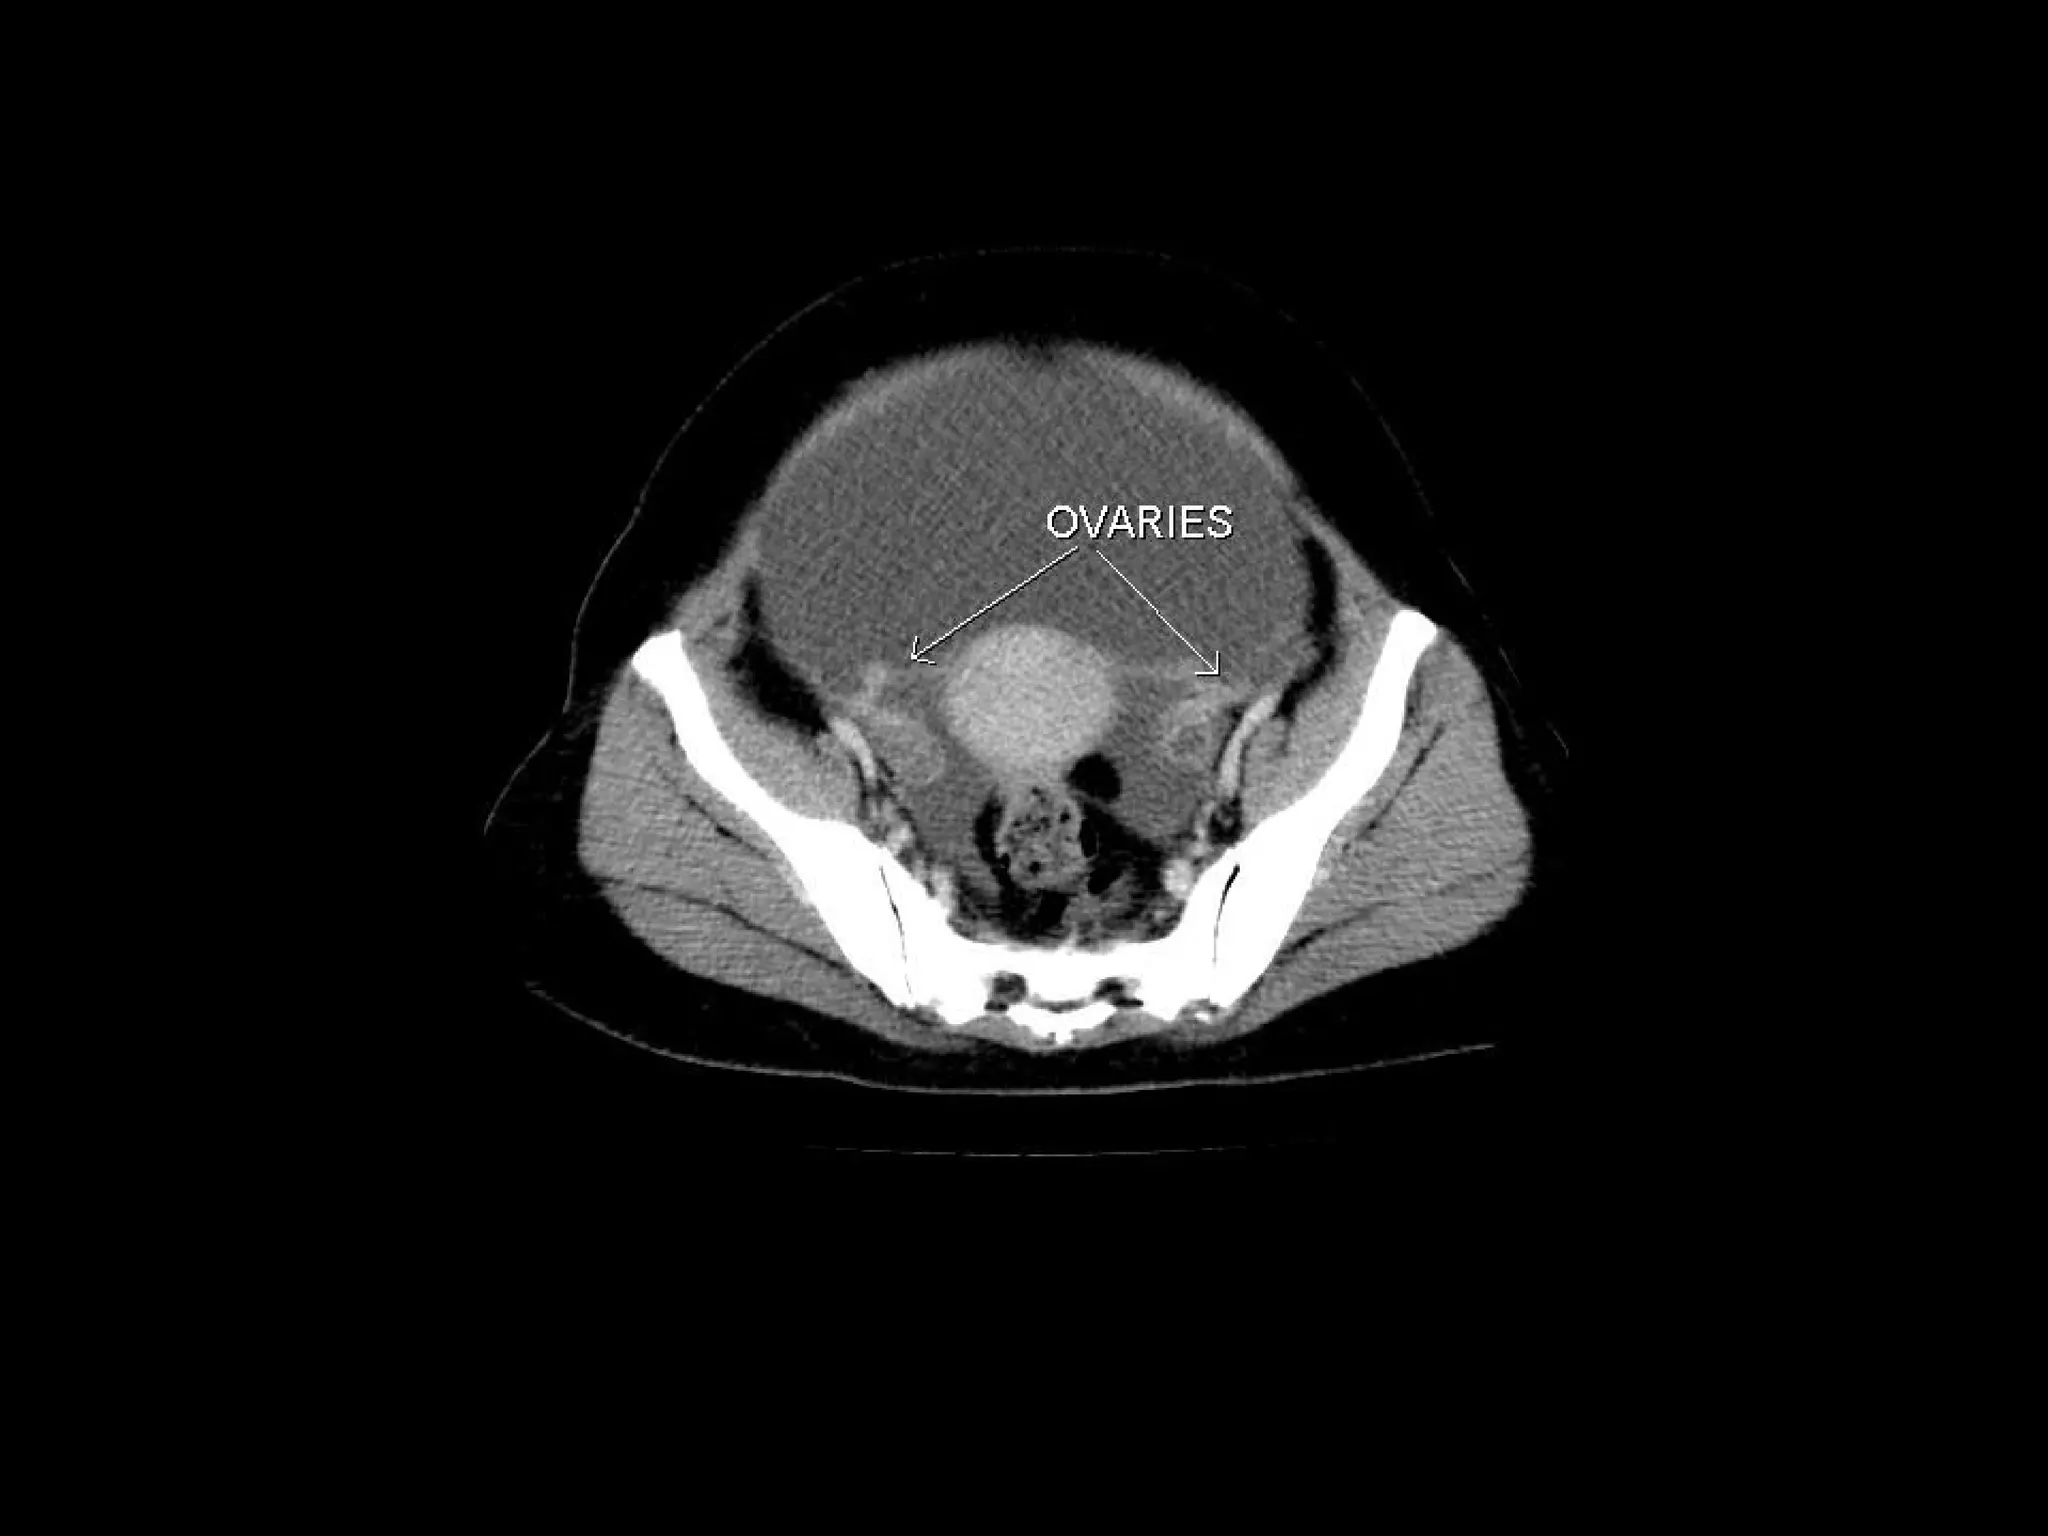

Radiographers are medical professionals who perform diagnostic imaging examinations and procedures to help physicians diagnose and treat diseases. They work under the supervision of radiologists to operate X-ray, CT, MRI, ultrasound and other medical imaging equipment and must have a strong understanding of human anatomy and pathology. Radiographers are responsible for correctly positioning patients, ensuring proper imaging techniques are used, and evaluating the quality of the resulting images.